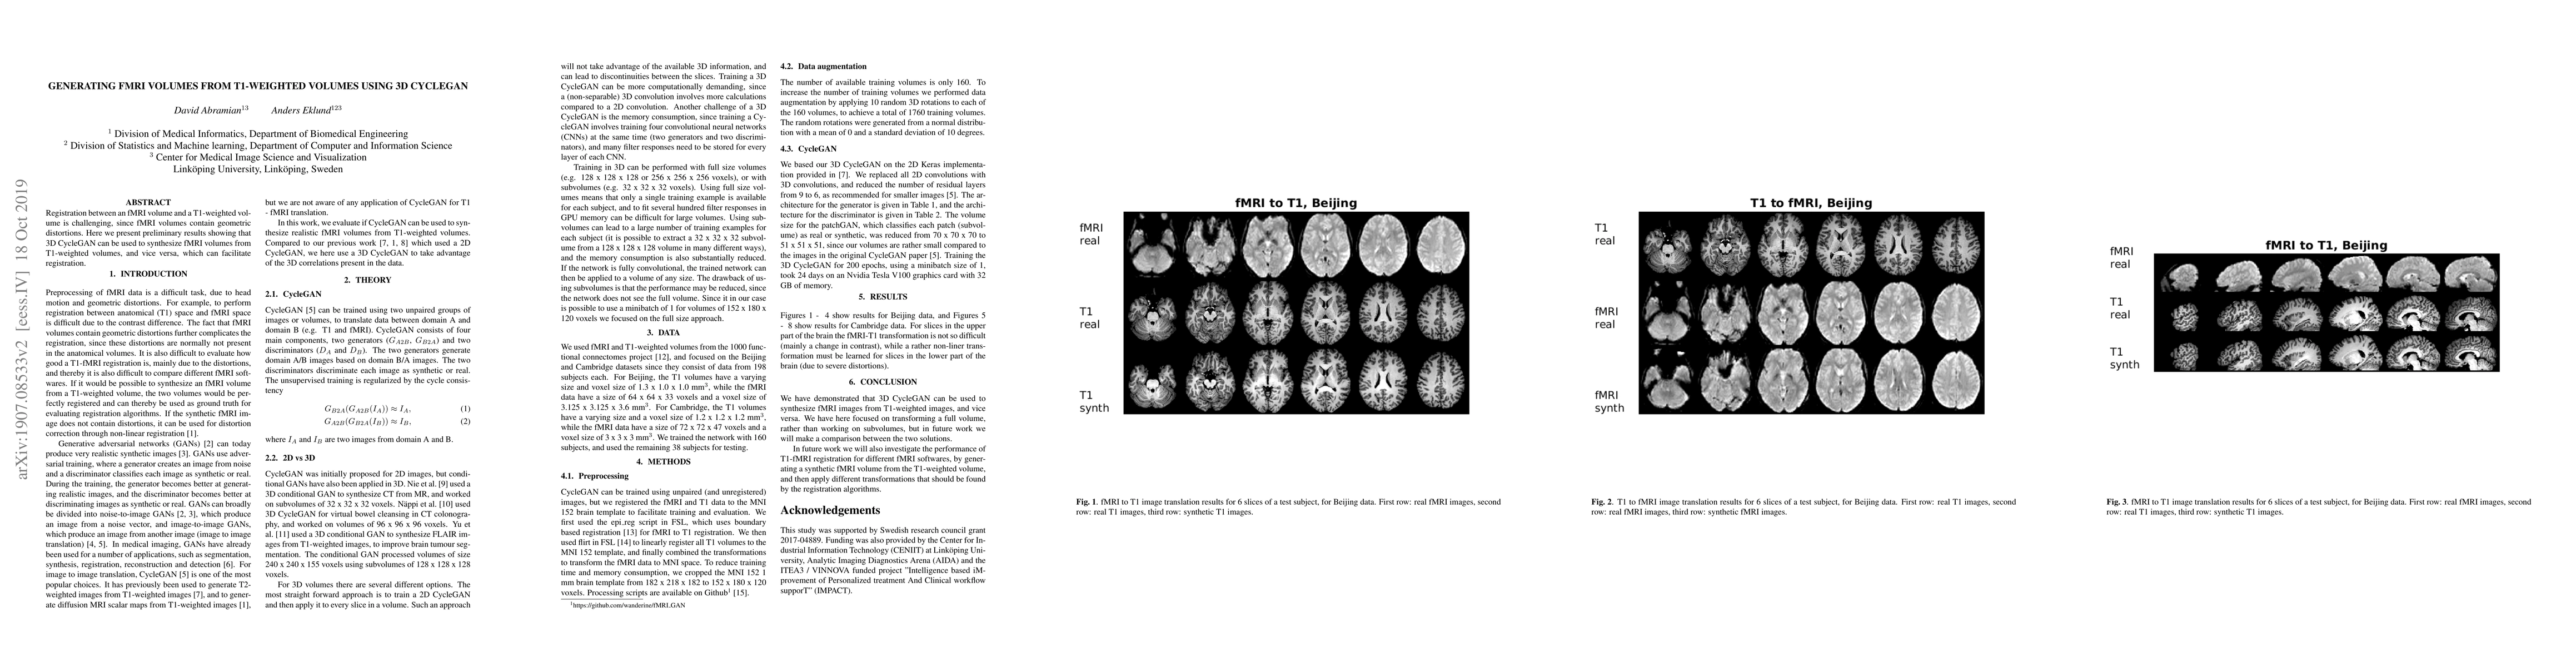

Registration between an fMRI volume and a T1-weighted volume is challenging, since fMRI volumes contain geometric distortions. Here we present preliminary results showing that 3D CycleGAN can be used to synthesize fMRI volumes from T1-weighted volumes, and vice versa, which can facilitate registration.